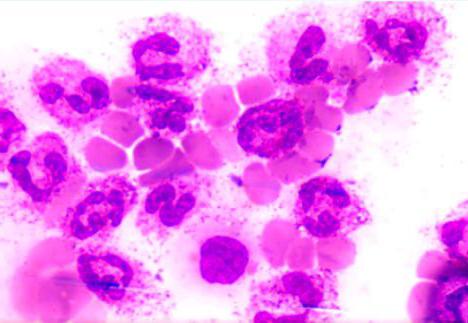

Эпителиоидные клетки образуются из мононуклеаров и макрофагов, скапливающихся в очаге туберкулезного воспаления в первые фазы воспалительной реакции. Они имеют крупное ядро овальной формы, обычно с 1—2 ядрышками Цитоплазма этих клеток содержит митохондрии, гранулы, аппарат Гольджи, хорошо развитую систему канальцев и цистерны зернистой и незернистой цитоплазматической сети, единичные фагосомы небольших размеров. Число митохондрий, элементов ретикулума, лизосомных включений широко варьирует и определяется функциональным состоянием клетки.

Гигантские клетки Пирогова—Лангханса могут образовываться из эпителиоидных клеток или макрофагов при их пролиферации, а также в результате слияния эпителиоидных клеток. Цитоплазма гигантских клеток содержит большое число ядер, обычно располагающихся в виде кольца или подковы по периферии клеток, множество митохондрий, лизосом, элементов зернистой цитоплазматической сети, хорошо развитый комплекс Гольджи. Гигантские клетки способны к фагоцитозу, в их цитоплазме обнаруживаются различные остаточные включения Они характеризуются высокой активностью гидролитических и дыхательных ферментов.

По своей природе гранулематозные узелки являются скоплением клеток, характерных для воспалительных процессов в тканях. Строение туберкулезных гранулем несколько иное. На первых этапах заболевания эти образования являются эпителиодно-клеточными, то есть, без некрозной зоны в центре. С прогрессированием недуга в центре туберкулезных гранулем появляется участок казеозного некроза. Вокруг него располагаются следующие клетки:

Эпителиоидные клетки

Эти структуры есть не что иное, как макрофаги, утратившие способность уничтожать чужеродные агенты, в данном случае палочки Коха. Строение туберкулезной гранулемы таково, что эпителиоидные клетки в ней располагаются вокруг зоны некроза в несколько слоев (иногда эта картина напоминает частокол), образуя циркуляционный ряд. Они довольно крупные, уплощенные, имеют большое ядро, крупное ядрышко и зозинофильную цитоплазму. В тех клетках, что ближе к зоне некроза, наблюдаются деструкция и дистрофия. В процессе своего образования эпителиоидные клетки проходят две стадии: незрелой и зрелой, что отражает кинетику дальнейшего развития гранулематоза.

Клетки Пирогова-Лангханса

Эти структуры образуются из клеток эпителиоидных двумя способами:

1. Путем цитодиэреза, что означает деление ядра без деления самих клеток. В результате в каждой из них может насчитываться более 100 ядер, располагающихся по периферии. Благодаря цитодиэрезу, их размеры получаются очень внушительными — до 50 мкм (по другим данным до 300 мкм) . Из-за большой величины, а также из-за многоядерности эти клетки туберкулезной гранулемы получили название гигантских. Также их называют клетками Пирогова-Лангханса.

2. Путем соединения эпителиоидных клеток.

Они считаются показательными для туберкулеза, хотя могут образовываться и при других заболеваниях. Решающим фактором для постановки диагноза является обнаружение в их цитоплазме палочек Коха или их фрагментов.

В цитоплазме гигантских клеток обнаруживаются лизосомы, митохондрии и окислительно-восстановительные ферменты. Если иммунитет человека, подхватившего палочки Коха, высокий, эти макроорганизмы ведут себя как фагоциты, то есть, уничтожают бактерии. В таких случаях усиливается клеточная пролиферация, и воспалительный процесс затихает. Если иммунитет низок, гигантские клетки образуют с бактериями своеобразный симбиоз, в результате которого заболевание прогрессирует.

Строение и клеточный состав

Клеточный состав такого образования разнится в зависимости от фазы развития и причин, вызвавших патологию. В туберкулезной гранулеме преобладает несколько типов клеток, отличающихся по строению и функциональной нагрузке. Эти клеточные структуры, выстраиваясь определенным образом, формируют туберкулезный бугорок. Его состав образуют лимфоциты, эпителиоидные клетки и клетки Пирогова-Лангханса, а также небольшое количество макрофагов. В центре гранулемы находится очаг творожистого некроза. Его формирование происходит внутри бугорка и соседних тканей, пропитанных экссудатом. Типичные туберкулезные бугорки с эпителиоидными клетками, а также лимфоцитами представляют собой своего рода частокол, расположенный вокруг казеозного очага. Помимо эпителиоидных клеток, очаг казеозного некроза окружен макрофагами и плазматическими клетками. Они образуют состав грануляционной ткани.

В состав туберкулезной гранулемы входят также клетки Пирогова-Лангхаса — огромные структуры, имеющие несколько ядер. Ученые полагают, что формирование таких специфических образований происходит под влиянием неизвестного патологического процесса из эпителиоидных клеток путем слияния нескольких ядер с сохранением цитоплазмы, либо путем слияния цитоплазмы в одну большую с сохранением ядер. Именно эти клетки свидетельствуют о туберкулезном процессе, их формирование является характерной особенностью гранулемы туберкулезного, а не иного генеза.

Туберкулезный бугорок имеет следующее строение: в центре бугорка аморфный тканевый детрит (следствие альтерации и некроза), по периферии расположен вал из нескольких слоев эпителиоидных клеток; во внешных слоях бугорка в небольшом количестве обнаруживаются лимфоидные клетки. Среди эпителиоидных клеток располагаются крупные многоядерные клетки Пирогова — Лангханса (рис. 3). По преобладанию того или иного типа клеточных элементов различают эпителиоидноклеточные, лимфоидные и гигантоклеточные бугорки. При высокой резистентности организма эпителиоидные клетки вытягиваются, превращаются в фибробласты и бугорок рубцуется. При снижении резистентности организма развивается экссудативная тканевая реакция с появлением творожистого некроза (казеоза), который может развиваться и в бугорке, и в окружающей его ткани, пропитанной серозно-фибринозным экссудатом. В дальнейшем очаг некроза может рассосаться, подвергнуться соединительнотканному замещению, обызвествлению и даже окостенению (оссификации).